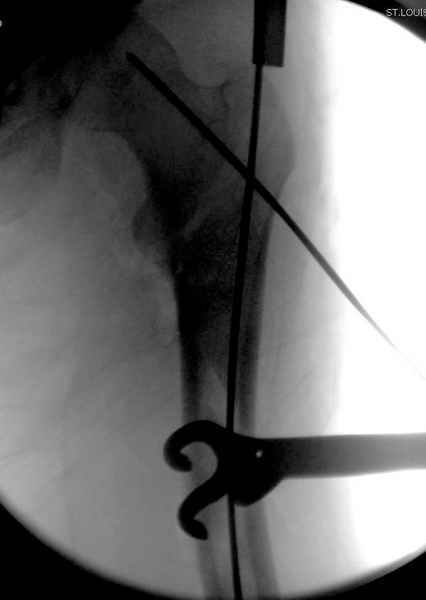

Как раз недавно у меня был примерный случай: больному 36 лет, поступил ночью, травма в результате мотоциклетной аварии, кроме чрезвертельного и спирального перелома левого бедра имеется переломы костей предплечья с этой же стороны. Скелетное вытяжение, а на следующий день больной про оперирован на ортопедическом столе с дистракцией. Чтобы не расколоть чрезвертельный перелом провели временную спицу ближе к переднему кортексу, из малого разреза костодержатель для репозиции, а фиксацию провели антиградным штифтом. Этапы операции на снимках.

Джолдас Кульджанов